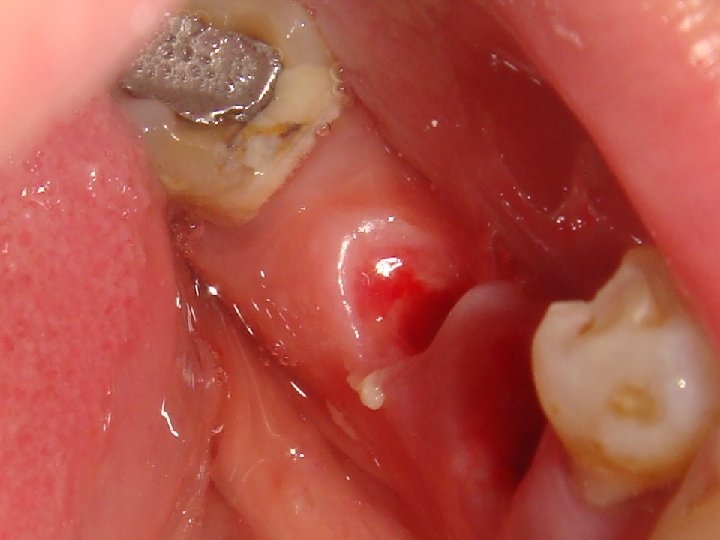

Abstract No. 1: A great challenge in implantology today is a predictable, long lasting red aesthetic result. An innovative treatment concept is based on a non-traumatic and effective shaping of the periimplant soft tissue – including an anatomical shaping from the first second. Especially, too many assembling and removing of abutments can contribute to aesthetic complications by vertical tissue loss. Therefore the “one abutment one time” and the “one crown one time” concepts are preferred. Additionally, platform switched and sealed implant-abutment connection prevent crestal bone loss and an apical shift of mid facial soft tissue.

Abstract No. 1: (cont. . ) In case of a fresh extraction socket the seal with the own tooth or a temporary crown can keep the complete soft tissue shape in a easy and predictable way. This "prosthetic" socket preservation simulates an intentional tooth reimplantation without the root. The same seal and therefore an optimal healing mode of the extraction socket is realized by an immediate implant insertion and restoration.

Abstract No. 1: (cont. . ) The lecture demonstrates a workflow for oral surgeons, prosthodontists and dental technicians to achieve a predictable midfacial soft tissue level by an effective and non traumatic protocol. Primarily results of a prospective clinical trial are promising. Additionally an insight into a scientific based explanatory model is given how a stable conical connection can increase the probability of a periimplant tissue preservation.